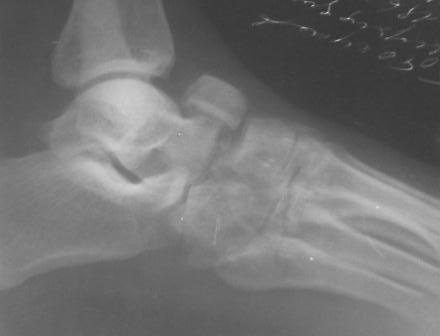

По данному случаю, оказалось 3 месяца назад было произведена Р-графия в райбольнице, но больной предпочел лечится у табиба. Присылаю первичные снимки.

Да, наш с Вами диагноз, Абдурашид, подтвердился. Я бы предпочёл артродез, фиксация- в самом простом варианте-винтами 3,5 или 4,5 . Отломок послужит аутотрансплантатом. Плюс внешняя иммобилизация. С уважением, Волна